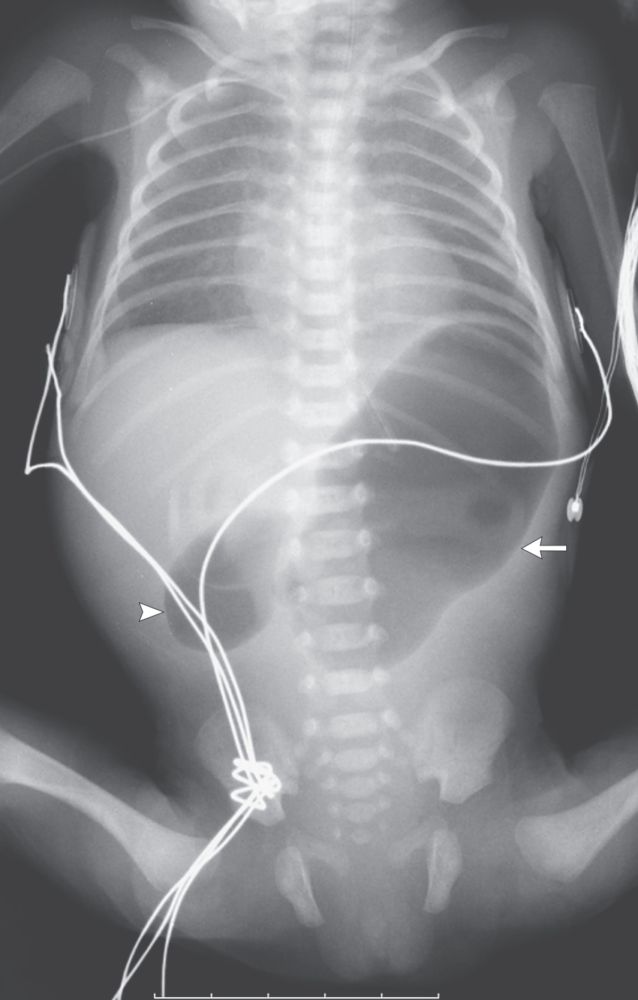

Abdominal radiography showed the double-bubble sign — a distended stomach (arrow) and proximal duodenum (arrowhead) — which is pathognomonic of congenital duodenal obstruction. There was no air distal to the level of obstruction in the D2 segment of the duodenum.